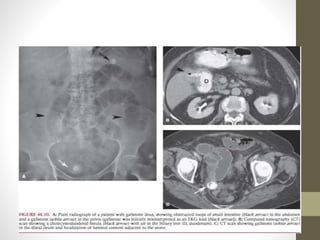

Íleo biliar

• Erasmus Bartolim en

1654

• 1-4% de obstrucciones

mecánicas

• Sospechar en:

• Cólico biliar recurrente.

• Historia de colelitiasis

• Fistula entre árbol

biliar e intestino.

• >2,5 cm

• Triada de mordor

• Historia de colelitiasis,

signos clinicos de

colecisitis y obstrucción

intestinal

• Localización

• Ileon 60.5%

• Yeyuno 16.1%

• Estomago 14.2%

• Colon 4.1%

• Duodeno 3.5%

• Extracción quirúrgica de cálculos + resección de tejido

intestinal necrótico.

• Recurrencia 5 – 10% en < 30 días.

• Controversia en colecistectomía y reparación fistula para

evitar recurrencia de íleo biliar y colangitis por reflujo .

• Consenso de colecistectomía en segunda intervención en

pacientes seleccionados.

Íleo biliar • ErasmusBartolim en 1654 • 1-4% de obstrucciones mecánicas • Sospechar en: • Cólico biliar recurrente. • Historia de colelitiasis • Fistula entre árbol biliar e intestino. • >2,5 cm • Triada de mordor • Historia de colelitiasis, signos clinicos de colecisitis y obstrucción intestinal • Localización • Ileon 60.5% • Yeyuno 16.1% • Estomago 14.2% • Colon 4.1% • Duodeno 3.5%

• Extracción quirúrgicade cálculos + resección de tejido intestinal necrótico. • Recurrencia 5 – 10% en < 30 días. • Controversia en colecistectomía y reparación fistula para evitar recurrencia de íleo biliar y colangitis por reflujo . • Consenso de colecistectomía en segunda intervención en pacientes seleccionados.